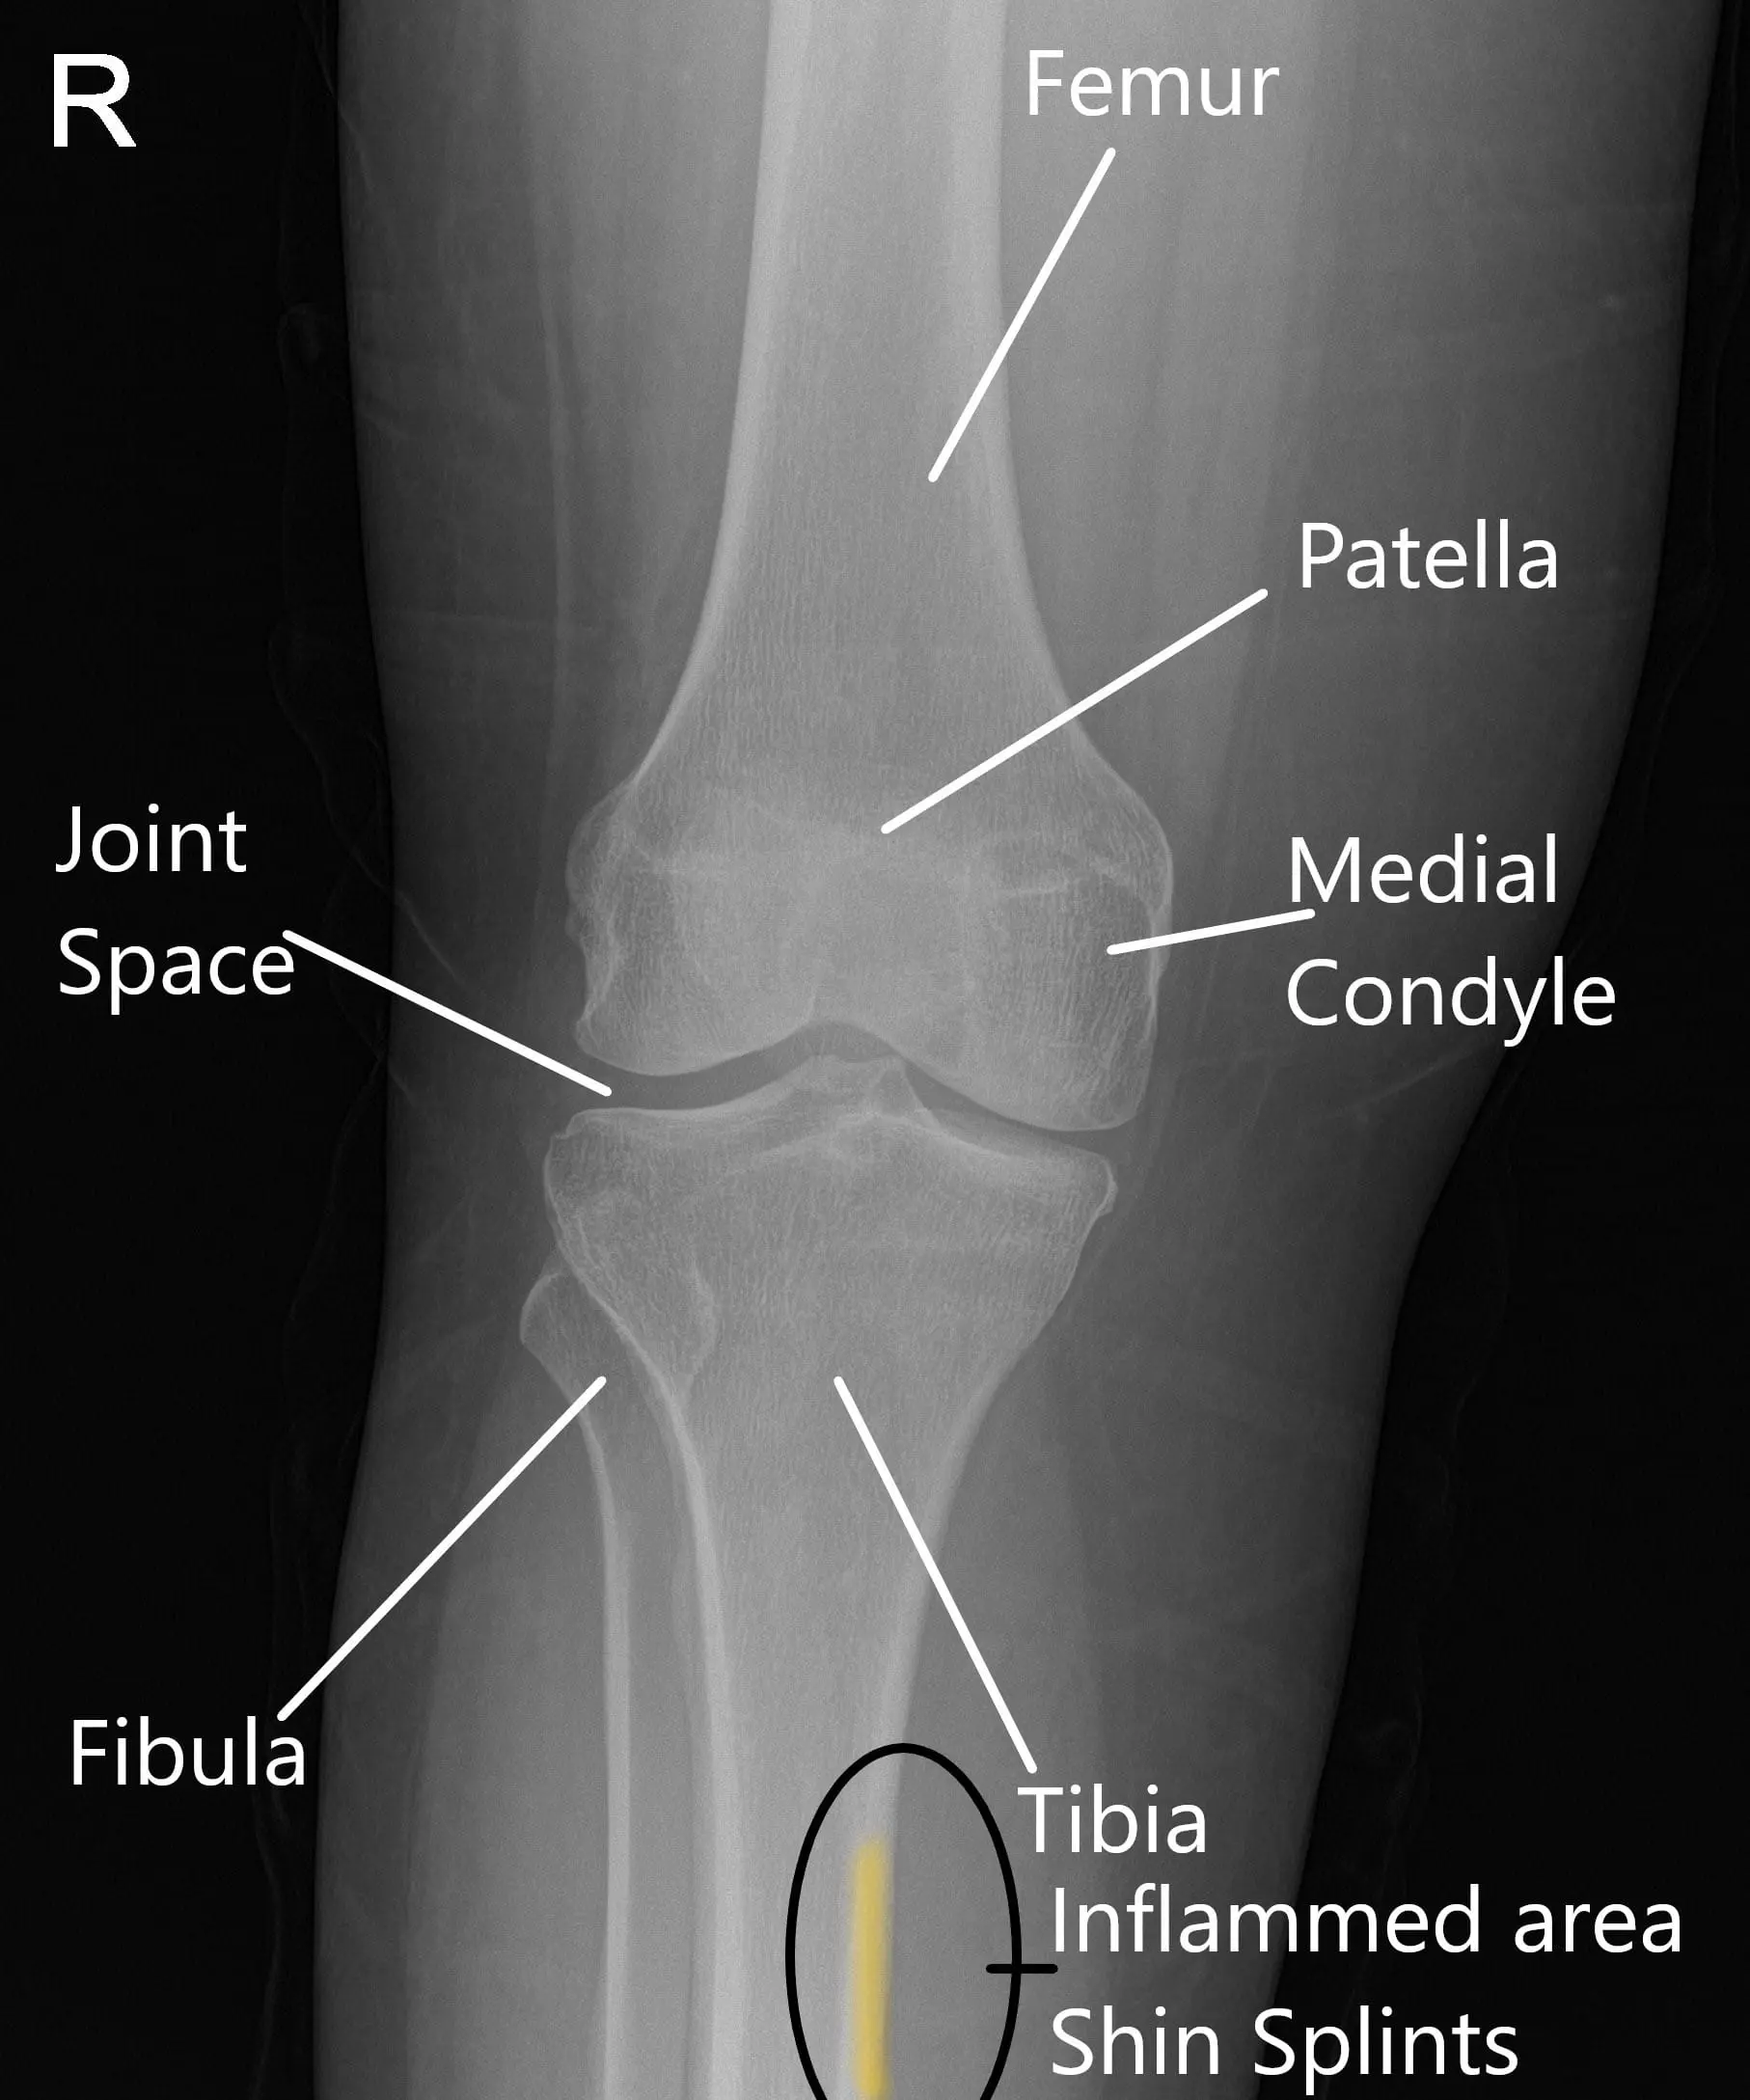

X-ray of a normal knee showing the area of inflammation in shin splints

X-ray of a normal knee showing the area of inflammation in shin splints.